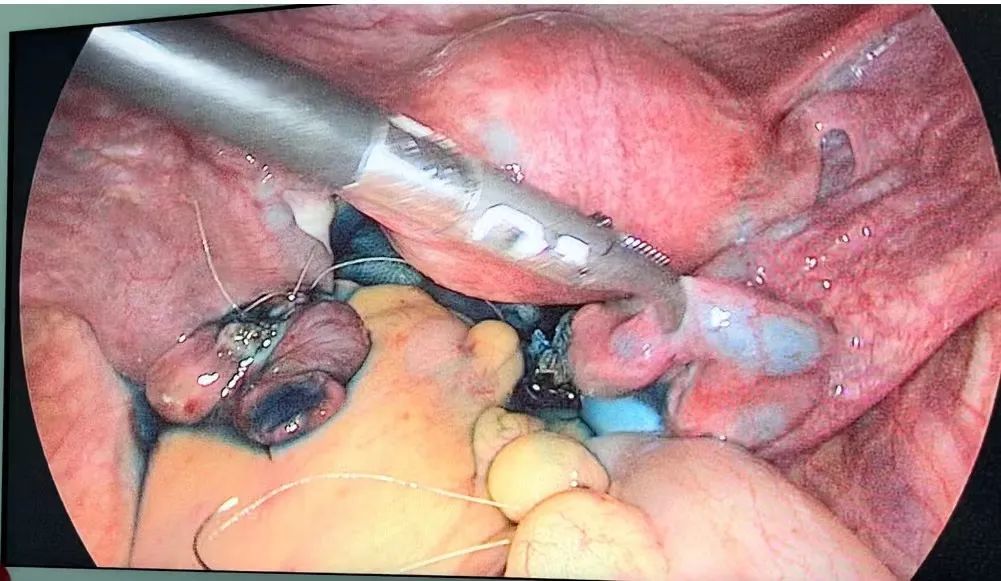

考慮病情較急,完善術(shù)前準備后急診在全麻下行腹腔鏡探查術(shù),術(shù)中探查見盆腹腔積血300ml,左輸卵管異位妊娠但未破裂,評估后考慮保留輸卵管是可行的!經(jīng)過切開取胚,完整取出輸卵管腔內(nèi)的妊娠組織及血塊,切除1cm粘膜粗糙的輸卵管組織并進行端端吻合,術(shù)中美蘭通液見雙側(cè)輸卵管無阻力順利流出!異位妊娠的輸卵管成功地保留下來!

雖保留了輸卵管還要警惕持續(xù)宮外孕的風險,術(shù)后必須定期監(jiān)測血HCG直至正常。患者術(shù)后第72小時復(fù)查血HCG454u/ml(術(shù)前HCG4950u/ml),術(shù)后病理:輸卵管取出組織為絨毛組織,支持宮外孕診斷,切除的部分輸卵管組織病理:未見絨毛組織。術(shù)后3天出院并門診監(jiān)測血HCG直至正常。1周后復(fù)查血HCG:68u/ml。